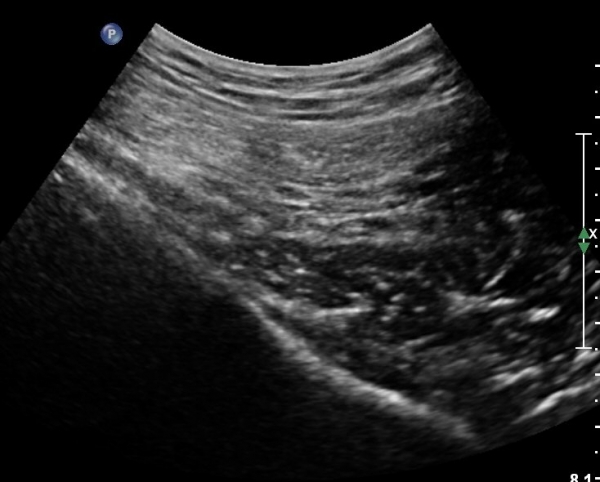

ŽÃÍÀÚ¸¦ ´Ù¸®ÂÊÀ¸·Î ¼öÆò À̵¿ÇÏ¸é ½ÉÃþ¿¡¼­ Àå°ñÀÌ »ç¶óÁö°í »õ·Î¿î ±ÙÀ°ÃþÀÌ º¸À̴µ¥ À̰ÍÀÌ ÀÌ»ó±ÙÀ̰í ÀÌ»ç±Ù ½ÉÃþ¿¡¼­ Á°ñ½Å°æ¸£ °üÂûÇÒ ¼ö ÀÖ´Ù(»çÁø 2, 3).